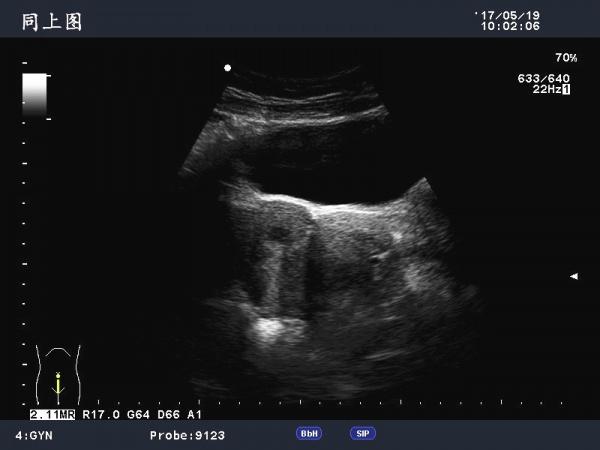

这是巧克力囊肿吗?

患者女,40Y,因下腹部疼痛就诊,最近一次月经来潮量少且疼痛厉害,以往基本上正常。

于月经第11天行B超检查。